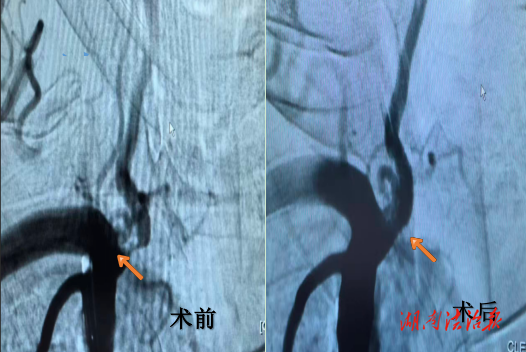

患者尹某,男,71歲,近3年來(lái)一直被反復(fù)發(fā)作的眩暈、視物模糊所困擾,走路時(shí)也感覺(jué)步履不穩(wěn)。經(jīng)全腦血管造影(DSA)這一“金標(biāo)準(zhǔn)”檢查,真相浮出水面:患者右側(cè)椎動(dòng)脈起始部出現(xiàn)了超過(guò)90%的重度狹窄!

10月31日下午,在導(dǎo)管室的通力協(xié)作下,蔣健、張?jiān)埔碜?zhèn)指揮,帶領(lǐng)神經(jīng)介入團(tuán)隊(duì)?wèi){借嫻熟的技術(shù),通過(guò)股動(dòng)脈穿刺,將細(xì)如發(fā)絲的導(dǎo)絲、球囊和支架系統(tǒng),精準(zhǔn)送達(dá)患者椎動(dòng)脈深部的狹窄病變處。首先,用球囊對(duì)狹窄部位進(jìn)行預(yù)擴(kuò)張,隨后,一枚精密的金屬支架被穩(wěn)穩(wěn)釋放,完美覆蓋了狹窄段。術(shù)中造影顯示:原本纖細(xì)如線的血管瞬間恢復(fù)了正常的管徑,血流變得通暢無(wú)阻。手術(shù)圓滿成功!